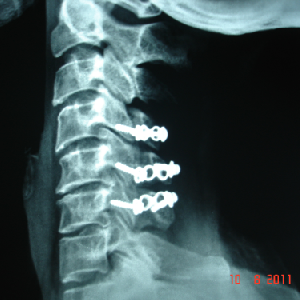

A very young pt of 25 years old, belonging to very good family, an engineer, had

tuberculosis of cervical

spine with destruction of C7 vertebra

if he would not get urgent attention and surgery, he could have landed up in developing

paraplegia

he was operated from front of the neck, a new vertebra(tricortical bone graft) was

put and fixed with plate

now he is doing very well in his life